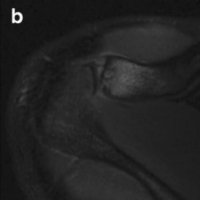

Pediatric traumatic hip dislocation are usually posterior and may occur due to low energy sports injuries in children less than 10 years of age. Hip dislocation are more common than hip fracture in pediatric patients and 80% are traumatic posterior dislocations.

Most of these cases can be diagnosed on AP pelvis films, which show loss of congruence of femoral head with acetabulum. Lateral view is sometimes is used to differentiate between anterior vs. posterior dislocation and to scrutinize femoral neck to rule out fracture prior to attempting closed reduction.

Treatment is urgent closed reduction under general anesthesia or sedation. Open reduction may be required if there is an intraarticular fragment following reduction. Post reduction imagings are necessary to inspect for joint incongruity or nonconcentric reduction.

MRI is a study of choice for any abnormal findings on post-reduction radiographs such as joint widening. In MR study, in inspect for joint incongruity or nonconcentric reduction. Entrapped labrum or capsule is best evaluated via MRI.

CT is second choice behind MRI for post-reduction evaluation, and also radiation exposure should be considered. Osteochondral fragments can be seen in older children and are easily detected by CT.

Delayed in reduction can lead to complications such as osteonecrosis, coxa magna, redislocation or nerve injury.